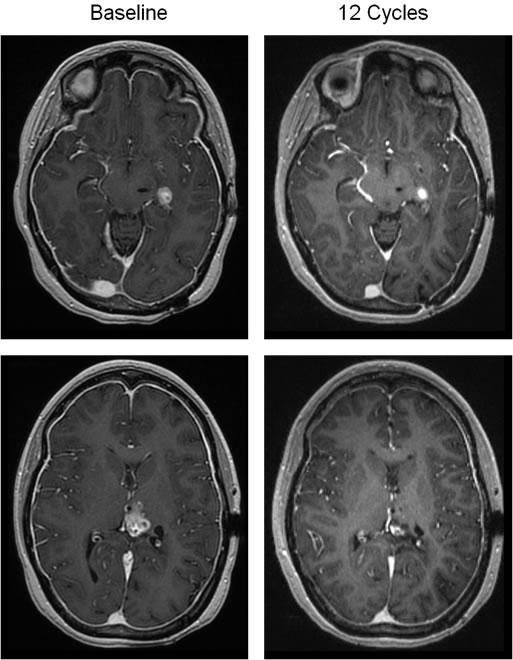

One 22 year-old female with a recurrent secondary glioblastoma that advanced from a H3.3 K27M mutant Grade III astrocytoma achieved a partial response by RANO occurring after 7 doses, and the response has been sustained for >6 months (Figure 2; Supplemental Figure 1). Two lesions were present at baseline that continuously regressed over time, with one lesion regressing approximately 85% in size compared to baseline after 8.4 months of therapy. The second lesion regressed to approximately 75% of the baseline size after 10.7 months of therapy. The second of these two patients who remain on study drug, a 52-year-old female who initiated ONC201 approximately 7 weeks after salvage surgery, remains disease-free for >11 months.

Figure 2: Objective response in a patient with recurrent glioblastoma. T1- post contrast brain MRI reveals two enhancing lesions at baseline (left top and bottom panels), which are decreased in size following 12 cycles of therapy (36 weeks; right top and bottom panels).